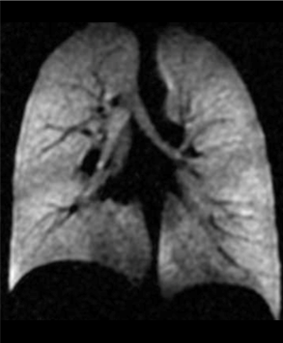

What is the study about?MAGNIFY is a research study funded by the CF trust that aims to look at the lung health of a variety of people with Cystic Fibrosis over time. To do this, we would like to take detailed pictures of the lungs using a type of clinical scan called Magnetic Resonance Imaging (MRI), which is able to detect small changes in the lungs when a special gas called Xenon is inhaled. It has been shown that these pictures are much better than the current breathing tests used in clinic to measure changes in the lungs.We would like to use these pictures to find out how well the new medicines in Cystic Fibrosis treat lung disease and ensure that when treatment becomes available for those who cannot take the new medicines, we are able to accurately measure any changes in the lungs following treatment. As well as the MRI scan, participants will be asked to perform a selection of breathing tests to access whether some breathing tests are able to better monitor lung disease in CF than what is currently used in clinic.

Here is an example of the pictures we can take of the lungs!